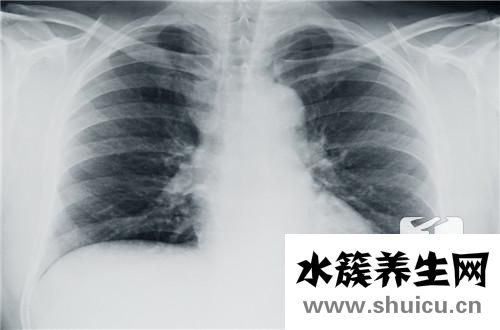

紅細(xì)胞是血液中運(yùn)輸營(yíng)養(yǎng)物質(zhì)和氧氣的一種細(xì)胞,紅細(xì)胞內(nèi)的血紅蛋白有氧和二氧化碳交換的功能,所以才讓人體可以呼吸氧氣維持正常的體態(tài)。紅細(xì)胞的數(shù)量和質(zhì)量正常對(duì)于健康來(lái)說(shuō)非常重要,如果紅細(xì)胞因?yàn)榧膊〉脑驕p少或者增加,都是不好的。那么紅細(xì)胞計(jì)數(shù)偏低引起什么后果呢?

如果不及時(shí)解決的話(huà),長(zhǎng)期的紅細(xì)胞計(jì)數(shù)偏低會(huì)導(dǎo)致氧的運(yùn)輸受阻。人體的紅細(xì)胞數(shù)減少,計(jì)算呼吸道足夠的氧氣,但是沒(méi)有足夠的紅細(xì)胞來(lái)運(yùn)輸氧的話(huà),人體會(huì)有缺氧的癥狀。最常見(jiàn)的就是容易頭暈、眼前發(fā)黑,甚至出現(xiàn)昏厥、如果人體處于缺氧狀態(tài),心臟的負(fù)擔(dān)也會(huì)增加,人體的各項(xiàng)技能都會(huì)降低。